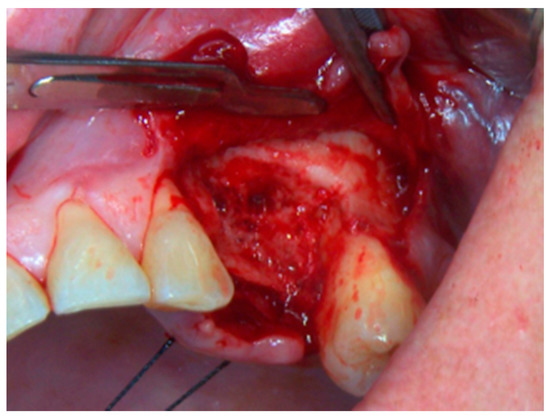

2. Materials and Methods

3. Results

4. Discussion